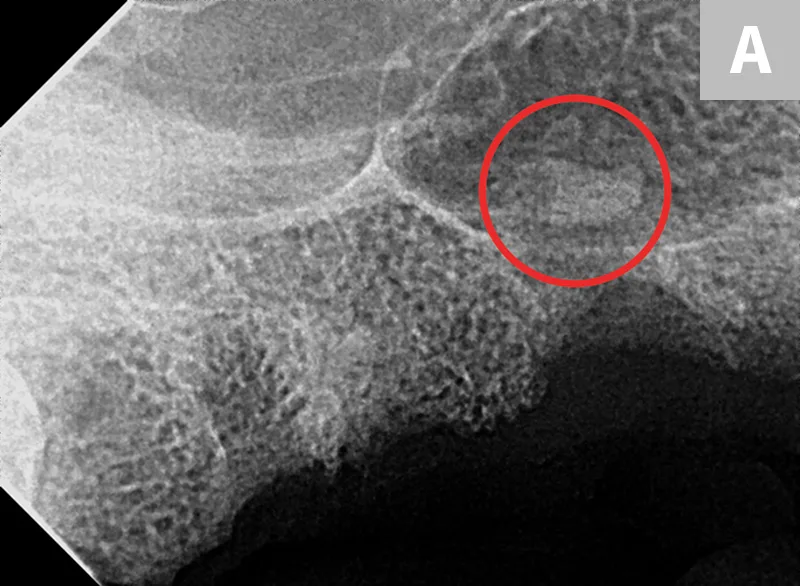

A potential sequela of root breakage is root tip protrusion into the nasal cavity (Figure 2) or mandibular canal (Figure 3),6 which, as with root breakage, can be caused by inadequate exposure or bone removal. In cases of root breakage, it is important to determine the location of the root tip and assess bone quality via dental radiography. If there is significant bone loss, a root fragment may be pushed through the apical extent of the alveolus and into an area that makes retrieval challenging. If this complication occurs and the root tip cannot be easily located, closing the extraction site and referring to a dental specialist is recommended.

FIGURE 2

Right maxillary premolar tooth root in the nasal cavity (A; circle) and root fragment after removal from the nasal cavity (B)

Root removal from the nasal cavity can be especially difficult because of the large size of the nasal cavity and the potential for tooth root migration. Large mucoperiosteal flaps, bone windows, and suction can aid in the removal process. Avoiding the mandibular neurovascular structures when removing roots from the mandibular canal can be challenging but is crucial, as hemorrhage can occur if structures are punctured.